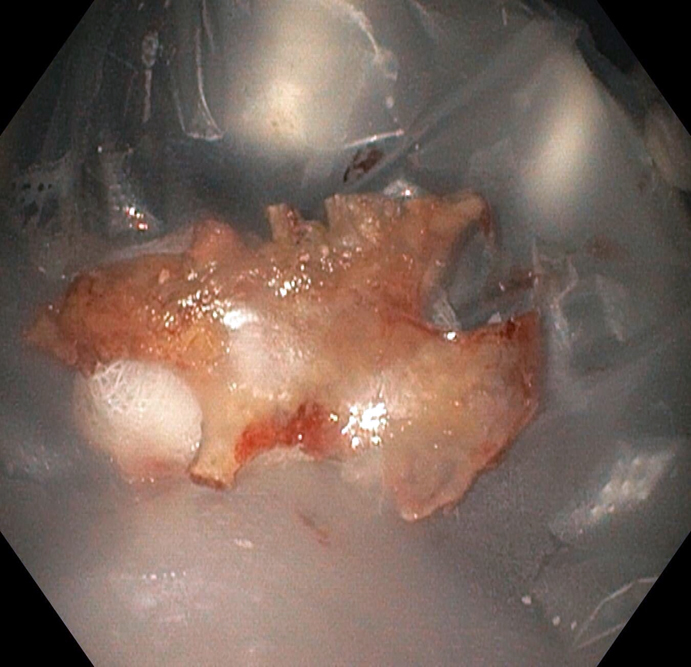

Khi tiến hành nội soi, các bác sỹ phát hiện có dị vật lớn cắm sâu vào thành thực quản, nghi xương gà.

Sau khi thông báo với người nhà, Bác sỹ chuyên khoa nội soi tiêu hóa Đặng Minh Trí, đã gắp ra một mảnh xương gà có năm đầu nhọn, kích thước khoảng 4 x 3 cm. Kiểm tra dọc thực quản xuống dạ dày không phát hiện thêm dị vật.